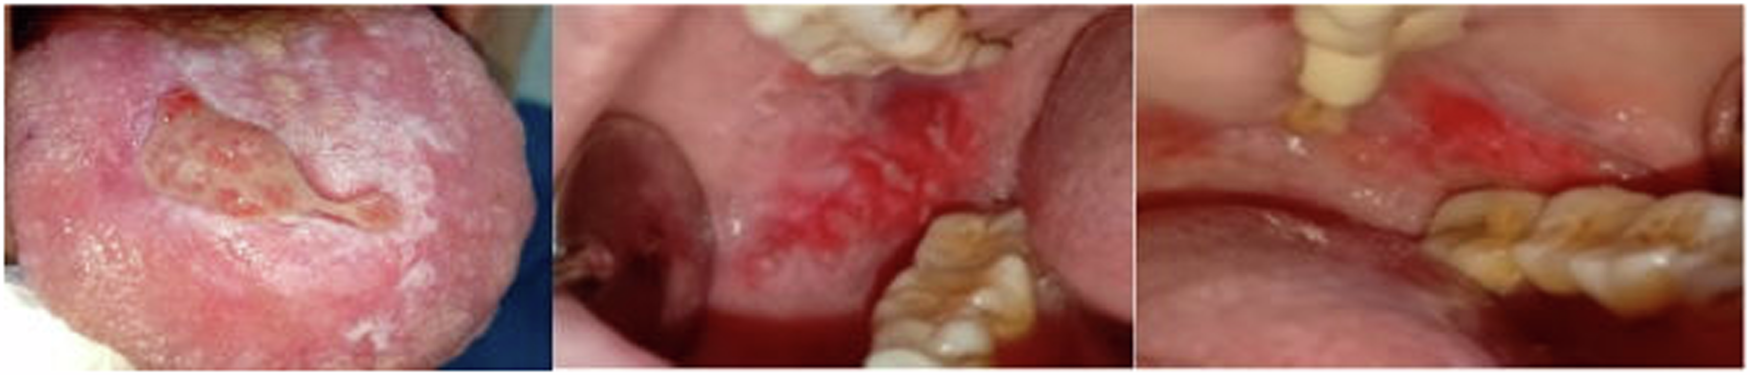

Fig. 2: Case No. 2. | BDJ Open